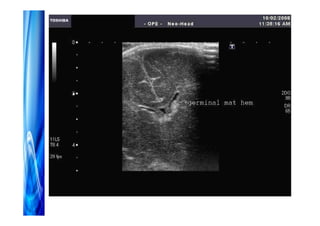

Diagnóstico precoce

Ultra-som de fontanela na 1a semana de

Diagnóstico precoce Ultra-som defontanela na 1a semana de vida